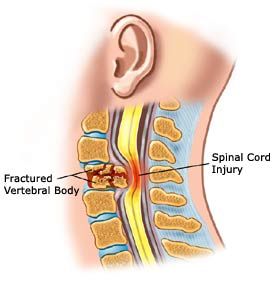

Spine surgery deals with any ailment which arises from the affliction of the spinal column, be it the vertebral bodies, the spinal cord or nerves, protruded intervertebral discs or joints.

Lumbar Radicular Pain is Back or neck pain that travels into the leg or arms respectively considered as radicular pain, especially when it is radiating below the knee and elbow which leads to a condition called sciatica in leg and brachialgia in arms. Commonly the systems are associated with back pain with symptoms such as tingling and numbness sensations, weakness, stiffness and occasionally involvement of bowel and bladder sensation commonly known as “Cauda Equina Syndrome”. It is a serious problem in the spine & an emergency where the pinched nerve roots have to be freed immediately.